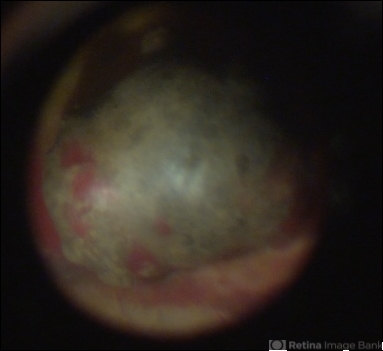

- chorioidal melanoma

- fundus photograph

- Fundus photograph of of a 52-year-old man with a choriod melanoma.